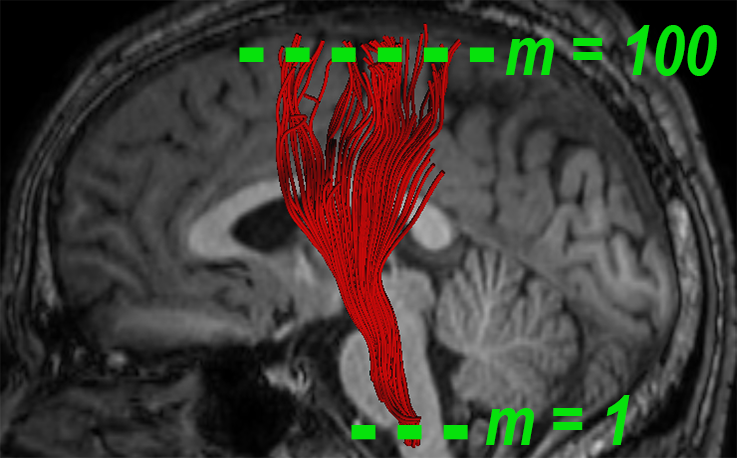

A fiber bundle can be thought of as a set of similar trajectories with a common origin and destination, along which water molecules are diffused [13]. In the spirit of this notion, we define a local measure for quantifying the fiber-flux of through a given plane , with normal at point , i.e.,

where is the number of intersected fibers, is the set of intersection points between the plane and the fiber bundle, and are the tangents of the fibers at those points. We call the fiber-flux density (FFD) of bundle at point . The plane is oriented such that the fiber-flux is maximized, i.e., . We use an iterative approach to solve this maximization problem in the spirit of [27]. We further introduce diffusivity properties into our model by extending the FFD measure. Let define a diffusivity scalar of choice (FA, MD, AD, or RD), associated with the point . We define the fiber-flux diffusion density (FFDD) as follows:

In practice, we refer to the FFDD as a vector to account for the local orientation of the fiber bundle. Note that the set of four FFDD descriptors (each assigned with a different diffusivity measure) couples diffusion measures with local geometrical features of the bundle. For example, local differences in orientation are taken into account, and regions with “incoherent” fiber orientations are “punished” by having lower FFDD values.

2.2 Along Tract Profiles

We calculate the mean fiber of the bundle , where is its arc-length parameter, based on Fourier descriptor [5]. According to this method, individual streamline fibers are represented by the coefficients of cosine series expansions, which are computed from tractography data using least squares estimation. The mean fiber is then optimally obtained by averaging the representation coefficients and applying the inverse transformation. The locations of the planar cross-sections along the bundle are determined by equidistant sampling points along the mean fiber . Tract-profiles are obtained by applying the FFDD descriptors along the tract, over these points.